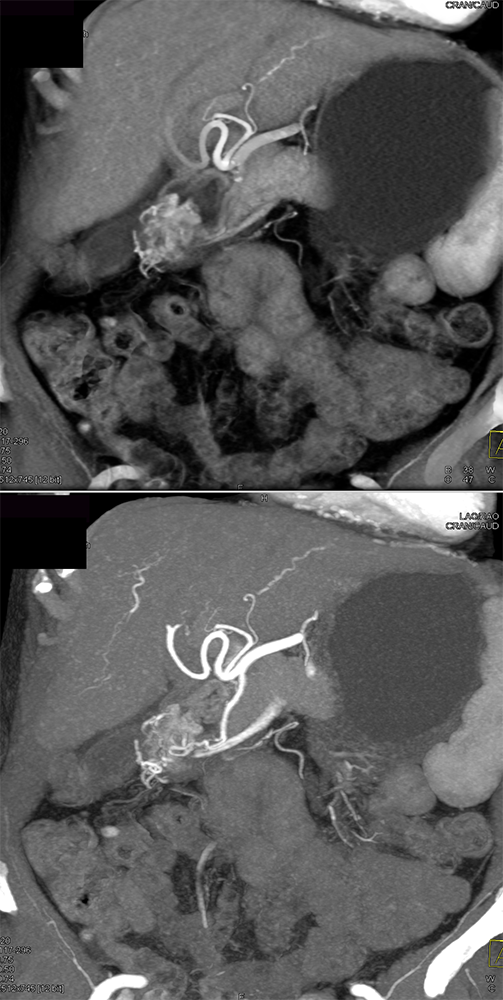

Suspected GI Bleed ![]() |

“In our patient, the findings of prominent mucosal folds extending from the pylonic channel on upper gastrointestinal series and the thickened antral wall on CT scans correlate well with the known pathologic appearance of gastnic antral vascular ectasia. Histologically, antral thickening results from a combination of foveolar and fibromuscular hyperplasia. Grossly, the antral fold prominence appears to result from bunching of the mucosa in the thickened, hypercontractile antrum.” Gastric antral vascular ectasia ("watermelon stomach"): radiologic findings. Urban BA, Jones B, Fishman EK, Kern SE, Ravich WJ. Radiology. 1991 Feb;178(2):517-8. |

Watermelon stomach (WMS), or gastric antral vascular ectasia (GAVE) ![]() |